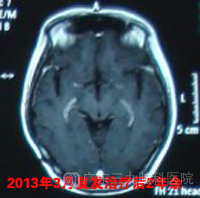

此后崔先生定期复查,期间见肿瘤逐步缩小,2010年5月复查头颅MR示原松果体区未见肿瘤复发,双侧颞叶,右侧额叶及胼胝体互补偏右多发异常信号影,2010年5月至10月再行3程化疗。此后复查复发部位病灶逐步缩小,未见其他部位新发病灶,目前已复发治疗后随访两年余,患者情况良好,颅内情况稳定,建议可1年后复查。www.999brain.com